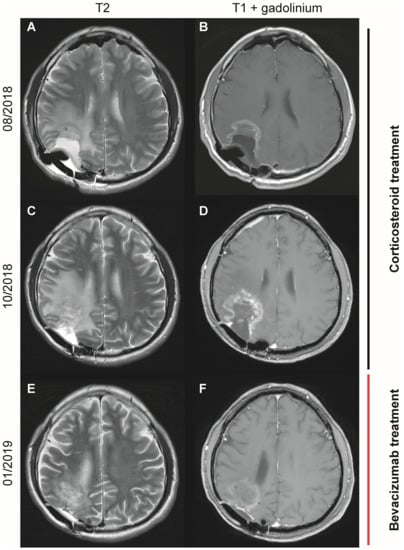

3.1. Successful Treatment of a Patient with Cerebral Radiation Necrosis with Subsequent Adrenal Insufficiency